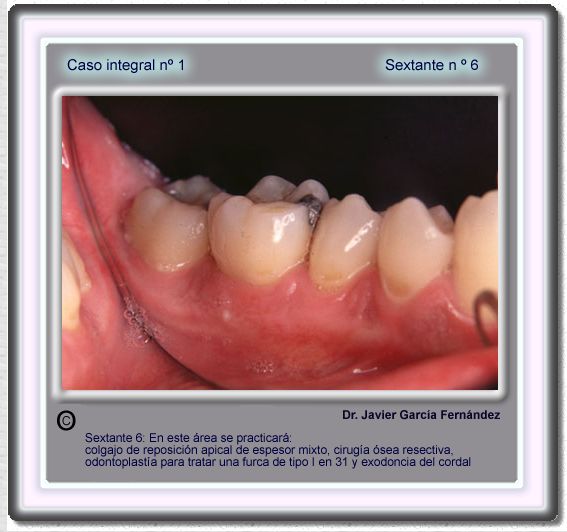

image 94